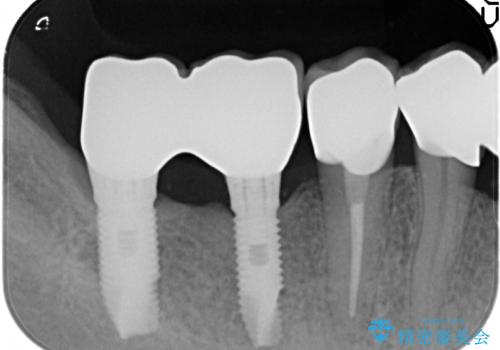

残すことのできる歯できない歯を選別し、欠損部にはインプラントによる咬合機能の回復、保存できる歯には歯周病治療・根管治療を行う治療計画としました。

銀歯がセラミッククラウンとなり見た目は美しくなりましたが、審美性だけでなく清掃性も向上し、歯ぐきの状態も良好で、歯周病の再発なく経過しています。